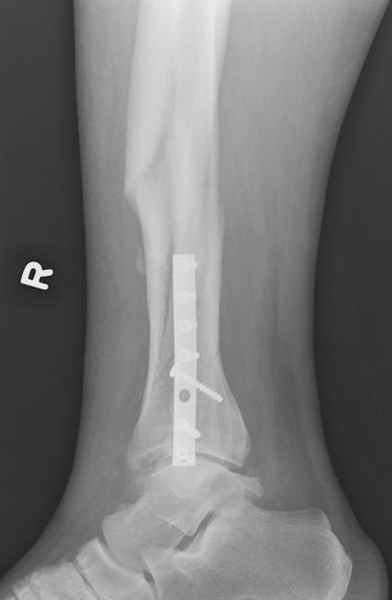

спрашивает что делать с больным который поступил недавно, фермер 55 лет падение при пьяной драке в баре, года два назад перенес операцию на лодыжке, на снимках и КТ перелом без вовлечения сустава,